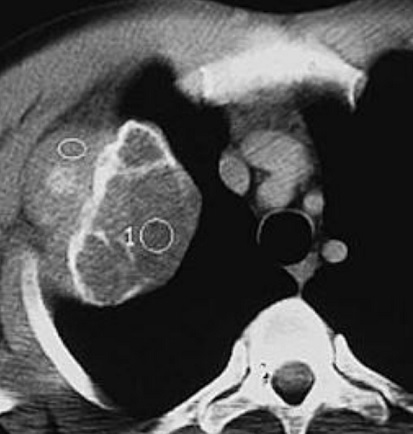

Aspect radiologique de tumeur

metastatique secondaire de type mixte ( lysis et

condensant) multiple disseminé à des côtes du thorax

et à la colonne vertebrale . Image radiologique TDM

en coupe axial , fenêtre mediastinale |